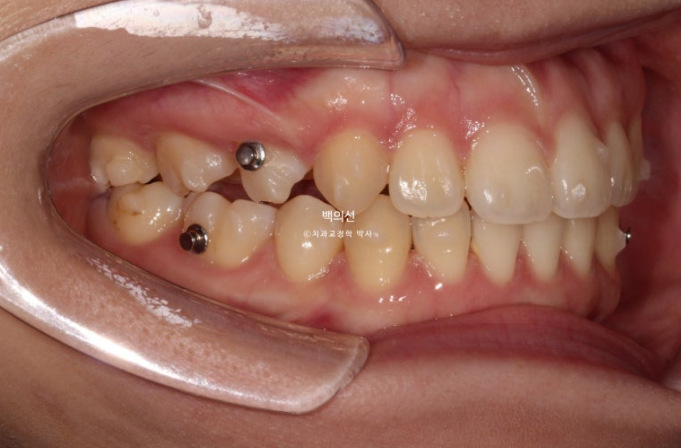

23.01

2년 전 인비절라인 교정치료를 위해 내원한 환자분입니다.

환자분이 고치고 싶은 것은

치아 비대칭

앞니로 면이 안 끊김 (개방교합)

두 가지입니다. 안모에서는 돌출입도 보였습니다.

23.05

고무줄을 걸며 인비절라인 치료를 진행합니다.